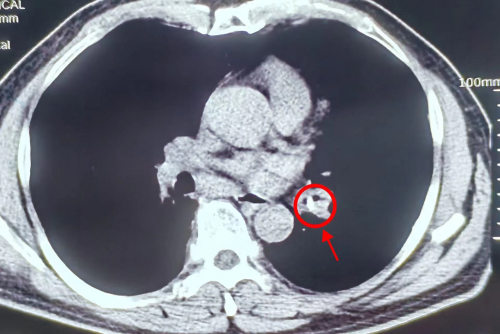

(影像检查发现患者的左下支气管有一块阴影)

3月11日,医生为刘大爷行纤维支气管镜检查,镜下见左下支气管的管腔基本堵塞,生理盐水冲洗后发现一个异物嵌顿紧密,在医护人员的紧密配合下,经过多次小心翼翼的尝试,异物终于被取出。清洗干净后,医生发现异物竟然是一块长约1.2cm的猪骨头。